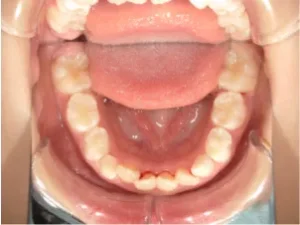

toshi_4_6